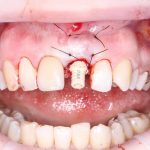

Установка формирователя десны, стандартного или индивидуального — это «классическое» завершение операции немедленной имплантации, поскольку, при условии хорошей стабильности имплантата и отсутствии проблем со слизистой оболочкой, разумно проводить формирование десневого контура одновременно с интеграцией имплантата. Фактически, это даёт возможность объединить все хирургические этапы в одну операцию, через несколько месяцев установить на имплантат коронку (для этого даже не требуется анестезия) и завершить лечение с минимальной травмой и максимальным результатом.

Но это еще не всё. Не каждый пациент готов оставаться без зуба на период проведения имплантологического лечения. Поэтому в некоторых случаях мы можем зафиксировать на только что установленный имплантат временную коронку, замок или даже целый временный протез: